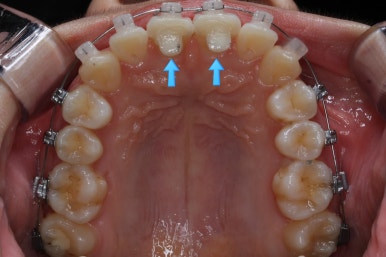

우선 윗니부터 가지런하게 합니다. 그리고 아랫니는 가지런하게 할 준비를 하죠.

화살표에 보이는 부착물의 이름이 바이트터보 입니다.

깊게 맞물리는 앞니, 즉 과개교합을 개선하기 위해 일시적으로 이용하는 장치입니다.

굉장히 효율적으로 과개교합을 개선할 수 있습니다.